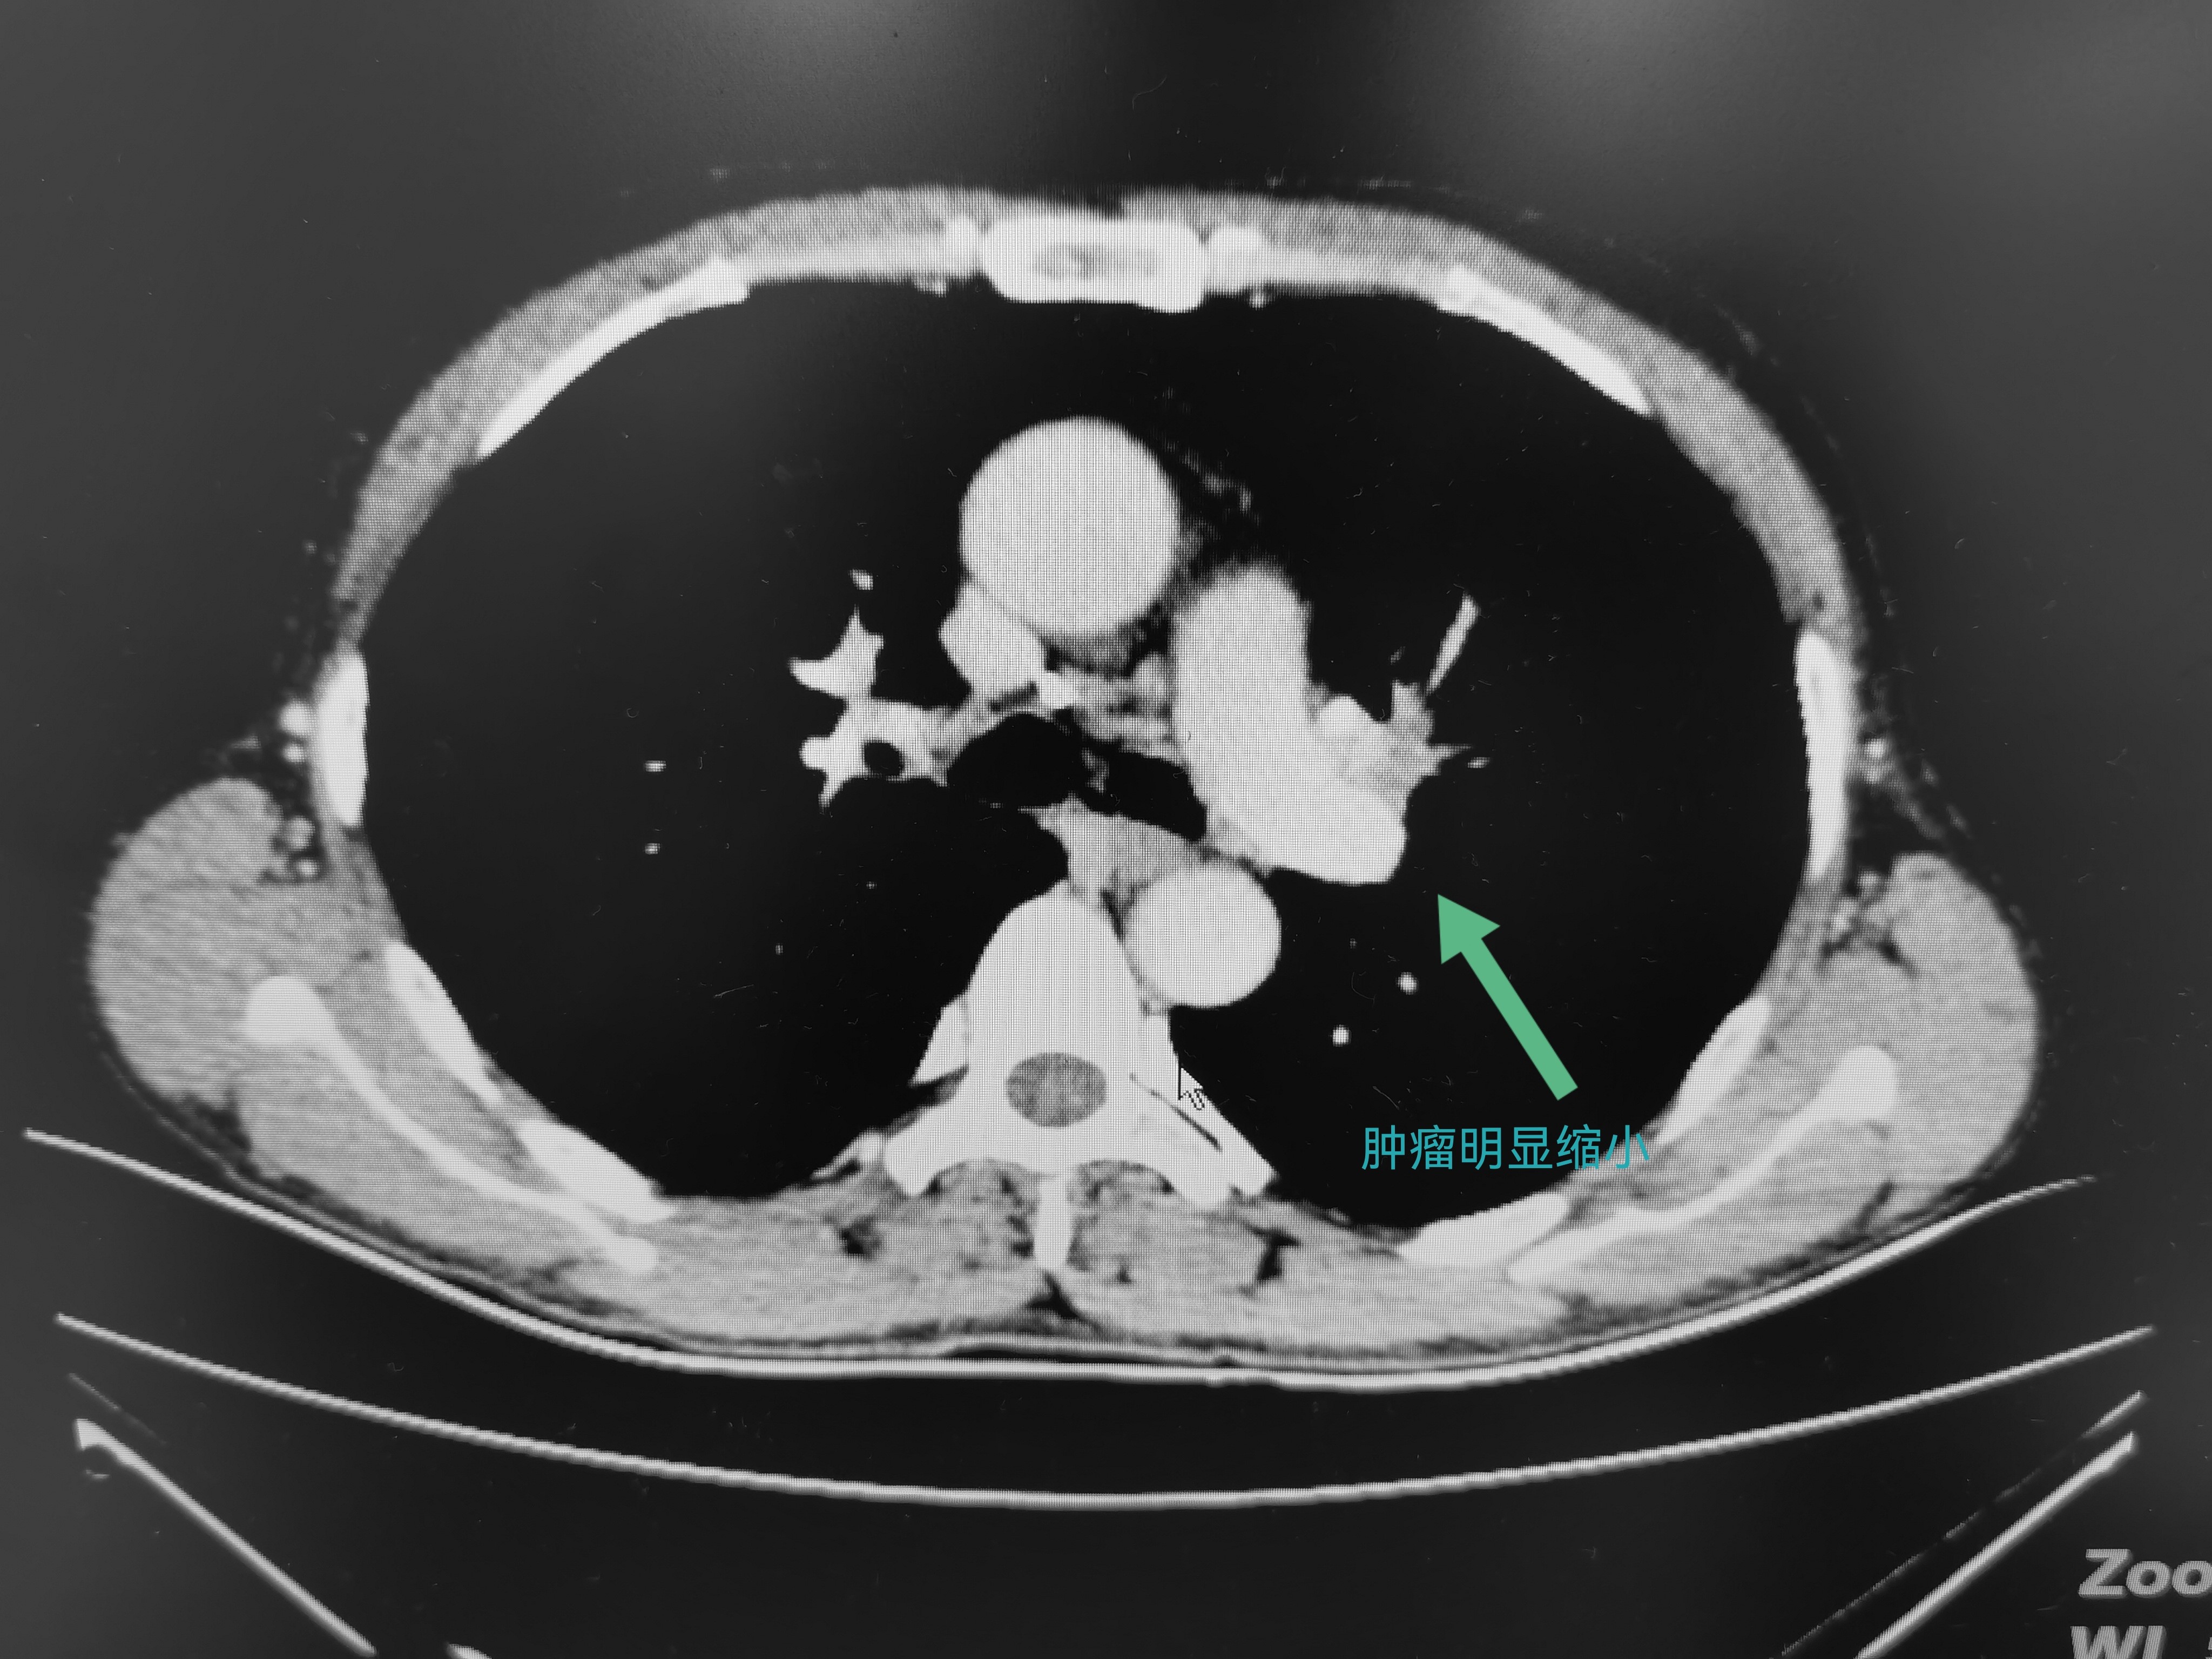

在新辅助治疗顺利结束复查时,刘爷爷的肿瘤已经缩小至2cm。这意味着,可以通过手术完整切除病变的左肺上叶,同时保留左肺下叶,以最大限度保障后续生活的质量。

新辅助治疗后